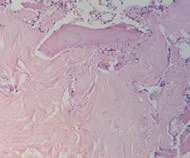

需要抽取一定的骨髓,在显微镜下计数骨髓涂片粒细胞与有核红细胞的比值。